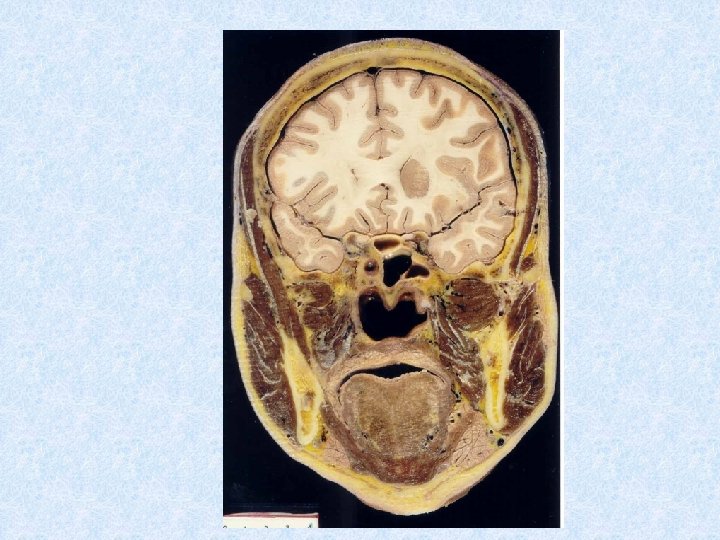

Section 2 Muscles of head ⅠFacial muscles 面肌

• Epicranius 颅顶肌 (occipitofrontalis) 枕额肌 – Frontal belly 额腹 – Occipital belly 枕腹 – Galea aponeurotica 帽状腱膜 • Orbicularis oculi • Buccinator 颊肌 • Orbicularis oris 眼轮匝肌 口轮匝肌 帽状腱膜 �腹

ⅡMasticatory muscles • Masseter 咬肌 – – – • Origin-inferior border and medial surface of zygomatic arch Insertion-lateral surface of ramus of mandible and angle of mandible Action-elevates mandible Temporalis 颞肌 – – – Origin-temporal fossa Insertion-coronoid process of mandible Action-elevates and retracts mandible • Medial pterygoid 翼内肌 • Lateral pterygoid 翼外肌